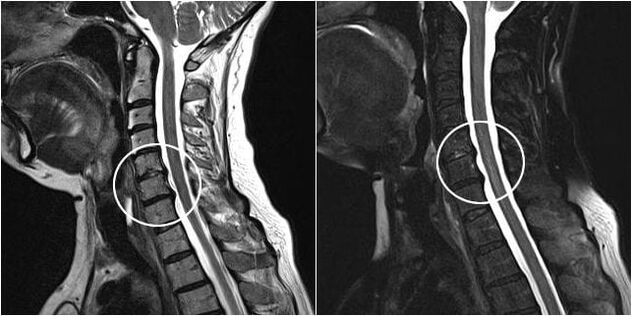

Surgery

Indications for surgery include ineffectiveness of conservative treatment, as well as complications of cervical osteochondrosis, for example, disc myelopathy, vertebral artery syndrome and radicular syndrome.To decompress the spinal cord, blood vessels and spinal roots, the following operations are performed:

During surgery, bone fragments and ligaments may be removed, and the intervertebral discs may be completely or partially removed.For small herniated protrusions, laser ablation of the disc core is often performed.

After resection of the vertebral structures, stabilization of the motion segments of the spine with spinal fusion or installation of bone and skin autografts is often required.